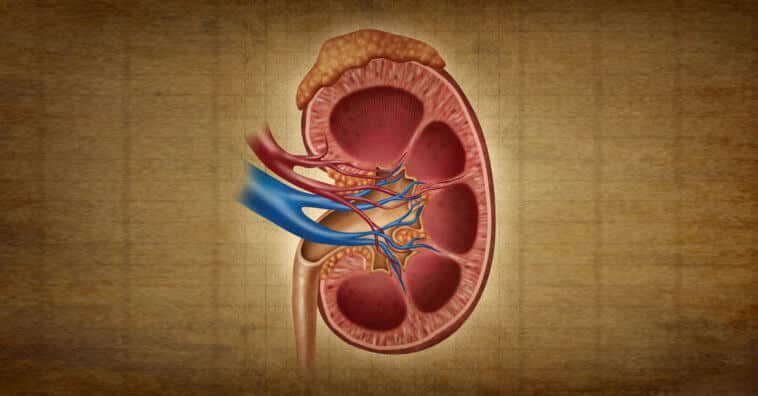

O rim artificial biônico é composto por filtros de silício e células vivas. Funciona em conjunto com o coração humano e múltiplos microprocessadores para filtrar o nosso sangue.

Ele é composto por células renais, daí que a sua rejeição esteja prevista para menos de 1%.